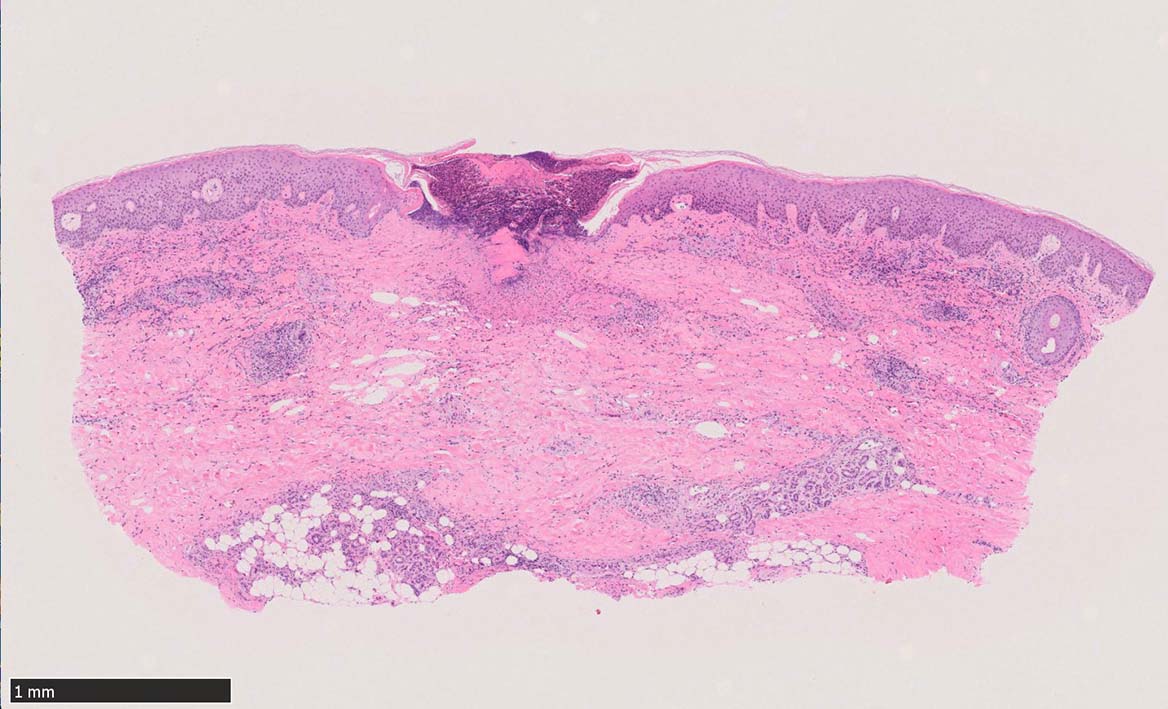

IWT-case01 66yo male. 3週間前(!)南アルプスに登山. 腹部皮膚のイボ様腫瘤に気づき来院。

マダニと思われる虫体を皮膚ごと切除した。

痂皮の下に硝子様凝固物があり, 周囲には壊死組織が形成されている. 近傍の細血管には凝固物による閉塞の所見があるように見える. 連続する細血管には, fibrinoid necrosisを呈する壊死性血管炎が認められる.